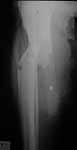

S/P Frame

Frame

Halt Trans

Regen Closeup

Placed on 6 wk course IV Ancef. (same pan sensitive bug at debridement). CRP, ESR normalized. Presently off abx. with no clinical signs of infection other than he's not making regenerate. I've halted transport and waited 4 wks with no real change. Any suggestions when not seeing regenerate. Any suggestions on stimulating regenerate? Thanks in advance for the input.